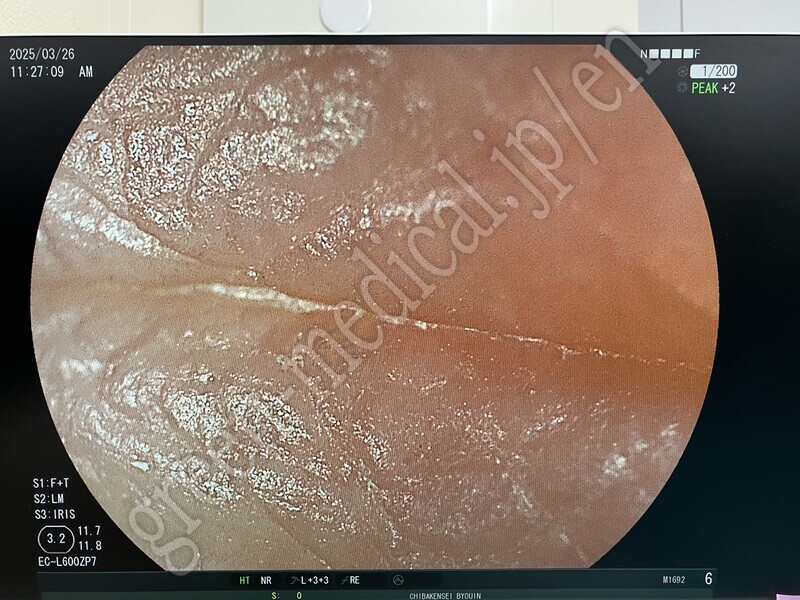

No Title .EC-L600ZP7

.EC-L600ZP7

FUJIFILM